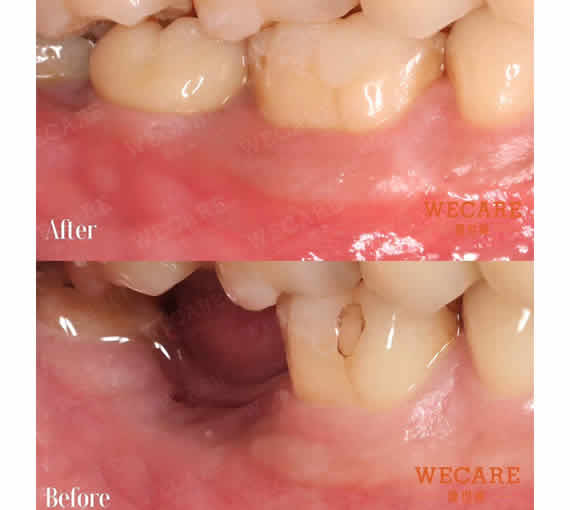

牙齦萎縮治療案例

牙齦不像牙齒那麼明顯,但卻是撐起整個口腔的重要基礎。當你開始察覺牙齦有變化,其實就是該安排評估的時候了。我們在桃園提供有彈性的看診與溝通方式,無論是否已有症狀,都歡迎從初步諮詢開始,重新認識牙齦健康!

牙齦萎縮指的是牙根不畏的牙齦萎縮,導致牙根暴露,影響口腔健康與美觀,且為很難完全恢復的症狀。牙齦萎縮較常見於中老年族群,但因口腔清潔狀況、齒列不整齊、飲食習慣等原因,近年牙齦萎縮、紅腫流血也有年輕化的現象。

您是否只要一吃到過冰或過熱的食物,牙齒就痠痛不適,讓美食體驗大打折扣?牙齒敏感絕大多數是因牙齦萎縮後牙根外露所致,萎縮的牙齦不但造成牙齒敏感、牙齦流血,也影響您笑容的美觀,且萎縮後的牙齦無法再回復,僅能細心維護不再持續惡化萎縮狀況。 藉由WECARE康世維的牙齦整形療程,能修復您暴露的牙根,讓您健康享受美食,展露自信微笑。